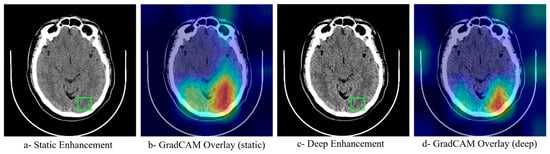

3.5. Model Interpretability

To understand how neural network optimization influences model decision-making, GradCAM activation maps were generated for both static and deep enhancement approaches. Figure 5 reveals that models trained on neural network-optimized images demonstrate more focused attention on clinically relevant regions, with activation patterns closely matching the anatomical locations of ischemic tissue. The optimized enhancement methods produced more coherent and interpretable activation maps compared to static parameters, suggesting that the improved classification performance stems from better feature extraction rather than artifact amplification. This interpretability analysis supports the clinical applicability of the deep enhancement approach.

Model interpretability analyses further support a mechanistic link between enhancement and improved decision making. Gradient- weighted Class Activation Mapping (Grad-CAM) activation maps (Figure 5) are more spatially focused and anatomically concordant with ischemic territories when the models are trained on neural network–optimized images, compared with static enhancement. The optimized pipeline concentrates attention within ASPECTS regions corresponding to the radiological ground truth, suggesting that performance gains are driven by better extraction of clinically relevant features rather than by artifact amplification. This behavior aligns with imaging studies where optimized preprocessing or texture preservation improves both classifier focus and downstream accuracy [12,18], and it supports the broader utility of Grad-CAM for verifying that models attend to disease-specific structures in medical images [23].

Figure 5. GradCAM Interpretability Analysis Comparing Attention Maps Between Static and Neural Network-Optimized Enhancement Methods. The green square denotes the clinically suspected ROI. Heatmap colors represent the level of model attention, where red/yellow indicate high activation and blue/green indicate low activation regions.